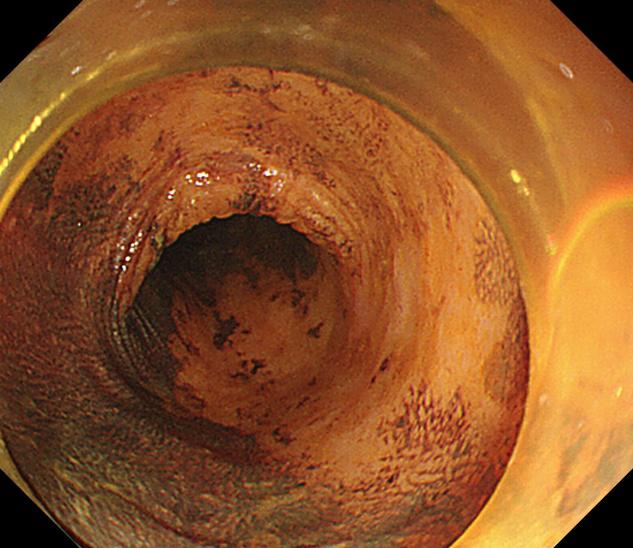

在随后一例肠镜检查中,一名中年女性患者结肠发现3枚无蒂锯齿状病变(SSL),该病变为结肠镜下极易漏诊的结肠癌癌前病变,我们用黄金刀成功施以内镜下黏膜剥离术(ESD)及内镜下黏膜切除术(EMR),完整切除结肠病变,根除了结肠癌的隐患!耗时仅仅10分钟左右,术后无并发症出现,同时送病理检查。

SSL(肠道锯齿状病变),多见于右侧结肠和回盲部,是大肠的癌前病变,癌变率大约10%。

内镜下观察平坦型较多,主要特征:黏液帽(黏液蛋白的缘故)、云雾状外观、扩张的II型腺管(Open II型)、分支扩张、蛇形的血管。当病变出现有蒂或亚蒂、隆起中有隆起、中央明显凹陷、病灶明显发红、合并IIIL、IV、Vi、VN型腺管表现时应想到癌变的可能性。